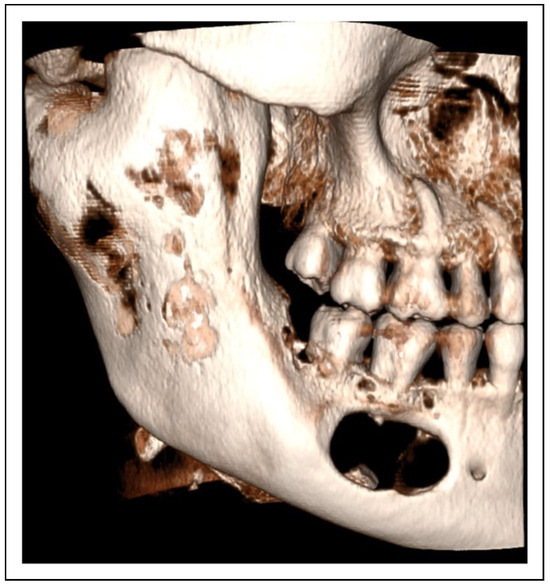

- Two-stage regime with simultaneous bone graft, patient 5